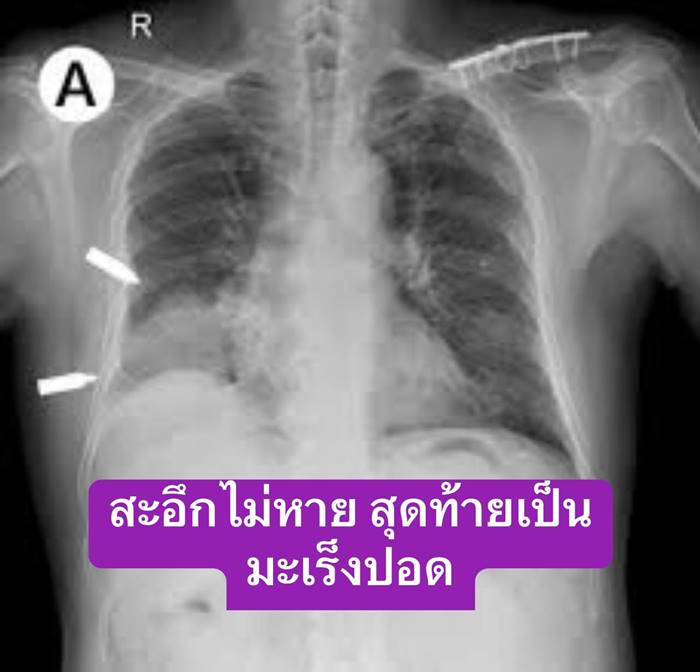

หมอสุรัตน์ เปิดเคสผู้ป่วยสะอึกไม่หาย ลองรักษาหลายวิธีไม่เป็นผล ก่อนเอกซเรย์พบมี มะเร็งปอด อยู่ตรงกระบังลม

โพสต์ดังกล่าวระบุว่า "สะอึก อย่าคิดว่าไม่สำคัญ" ที่คุณหมอบอกว่า หากมีอาการสะอึกบ้าง วิธีการแก้คือให้หายใจในถุง กินข้าวกินน้ำ เพื่อให้กระบังลมกลับมาสัมพันธ์กับการหายใจ แต่มีคนไข้รายหนึ่งซึ่งเป็น Case Report คนไข้มีอาการสะอึกไม่หาย กินข้าว กินน้ำเท่าไรก็ไม่หาย แม้จะรับประทานยาแก้สะอึกเข้าไป จนสุดท้ายผ่านไปหลายวันและไปเอกซเรย์ หมอบอกมีก้อนที่ปอดเป็นมะเร็ง..

โดยคนไข้รายนี้ พบมะเร็งที่กระบังลม จนทำให้ระคายเคือง และการหายใจไม่สัมพันธ์กับการเคลื่อนไหวของกระบังลม จนสะอึกไม่หาย

"ไม่นึกไม่ฝัน กับแค่สะอึกเนี่ยนะ มะเร็งปอด บางทีมันอยู่ตรงกระบังลม ทำให้ระคาย และการหายใจไม่สัมพันธ์กับการเคลื่อนไหวกระบังลมทำให้สะอึก โรคร้าย ๆ บางที ก็มาด้วยอาการง่าย ๆ แบบนี้"